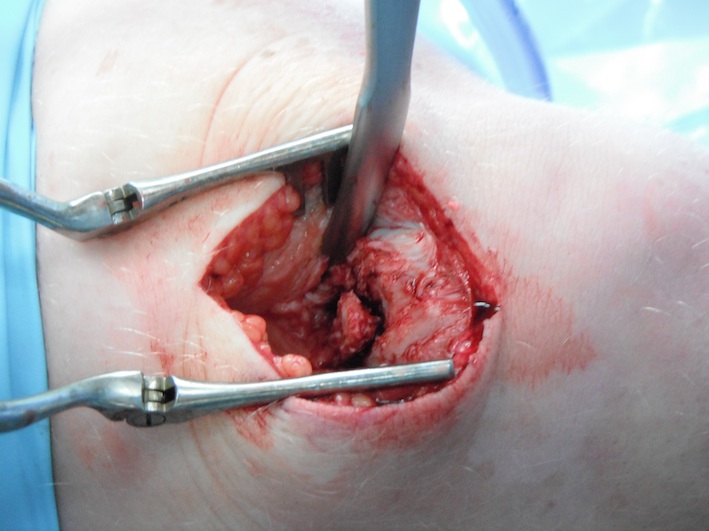

Removal of bipartite patella

A. Open

- easiest

- often need to reattach quadriceps tendon with anchors